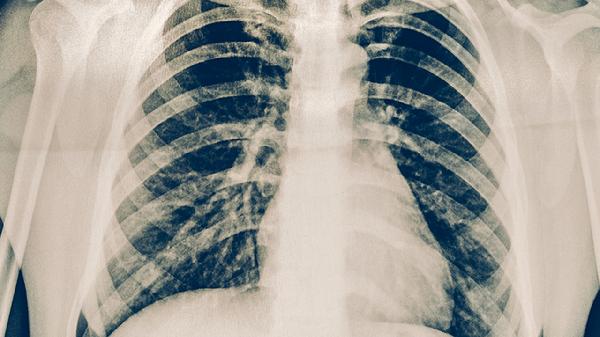

轻微肺结核患者可遵医嘱使用异烟肼片、利福平胶囊、吡嗪酰胺片、乙胺丁醇片、链霉素注射液等抗结核药物。肺结核是由结核分枝杆菌感染引起的慢性传染病,需规范联合用药以降低耐药风险。

肺结核患者应保证充足营养摄入,每日补充优质蛋白如鸡蛋、鱼肉,多食富含维生素C的西蓝花和柑橘类水果。保持居室通风良好,咳嗽时用纸巾掩住口鼻,痰液需消毒处理。严格遵医嘱完成6-9个月规范治疗,不可自行停药,定期复查胸部影像学和痰菌检查。出现药物不良反应应及时就医调整方案,治疗期间避免与婴幼儿密切接触。